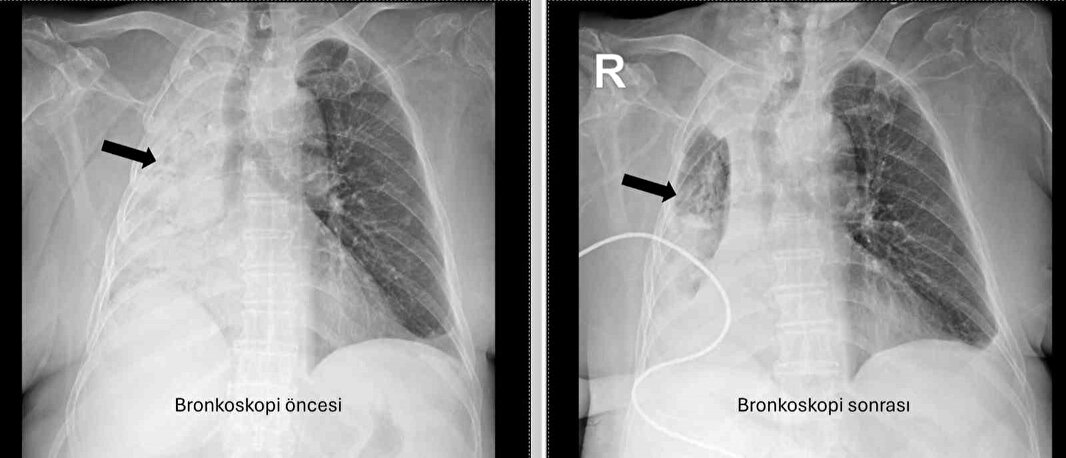

Denizli’de 78 yaşındaki felçli hastanın nefes borusuna kaçan mısır tanesi 5 ay sonra ortaya çıktı. Akciğerine enfeksiyonu şikayetlerinin tekrarlamasıyla ortaya çıkan olayda, yaşlı kadının sağ akciğerinin tamamen kapalı olduğu anlaşıldı.

PAÜ Hastaneleri Göğüs Hastalıkları Anabilim Dalı Öğr. Üyesi Prof. Dr. Göksel Altınışık Ergur, tarafından yapılan tetkiklerde sağ akciğere giden hava yolunun bütünüyle kapalı olduğu görüldü.

“Fleksibl (esnek, eğilip bükülebilir) bronkoskop ile hava yolları incelenirken çok yoğun ve koyu sekresyon olduğu, bunun iyice temizlenmesi sonucunda ancak hava yollarının incelenebileceği görüldü. Aspiratör (içerideki salgıları emmeye yarayan bir cihaz) sayesinde hava yollarına steril sıvı verilip emilerek bu temizlik yapıldı. Sonrasında sağ akciğere giden hava yolunda sarı bir nesne olduğu görüldü. Bu hâliyle yabancı cisim olduğu anlaşıldığı gibi bunun mısır tanesine benzerliği de açıktı. Yabancı cismi çıkarma işlemi genel anestezi altında, rijit bronkoskop ile yapılmak üzere planlanabilirdi; çünkü bu durumun tedavisi yabancı cismin oradan, ek sorun oluşturmaksızın çıkarmaktı. Ancak, genel anestezi altındaki bir işlem için hastanın genel durumu bozuk olduğundan, özellikle ek hastalıkları ve enfeksiyon varlığı ile işlem riski artacağından hastadaki cismin fark edildiği sırada çıkarılmasına şans vermek daha uygun görüldü.

Hava yolu içindeki sıvıları emen aspiratörün gücünü kullanılarak cismin çıkarılması mümkündü. Bronkoskobun ucu, sarı cismin gövdesine dayanıp aspiratör ile emme sayesinde ikisi birbirine sımsıkı yapıştırıldı. Emme gücünün azaltılmamasına dikkat ederek yabancı cisim ve bronkoskop, aynı zamanda hava yollarından dışarıya başarı ile çıkarıldı. İşlem sonrasında hasta yakınına mısır tanesi açısından tıbbi öykü yeniden sorulduğunda, hastamızın bundan beş ay önce yediği pizzanın üzerinde mısır taneleri olduğu öğrenildi. O sırada ani bir yakınma ortaya çıkmadığı için böyle bir ihtimal akla gelmemişti. Düşkün hastalar taneli gıdalar yerken, bu durumun fark edilmeden de gelişebileceğini göstermesi açısından önemli olan bu tablo, hastaların bir dedektif titizliği ile değerlendirilmesi gerekliliğini bir kez daha ortaya koymaktadır”